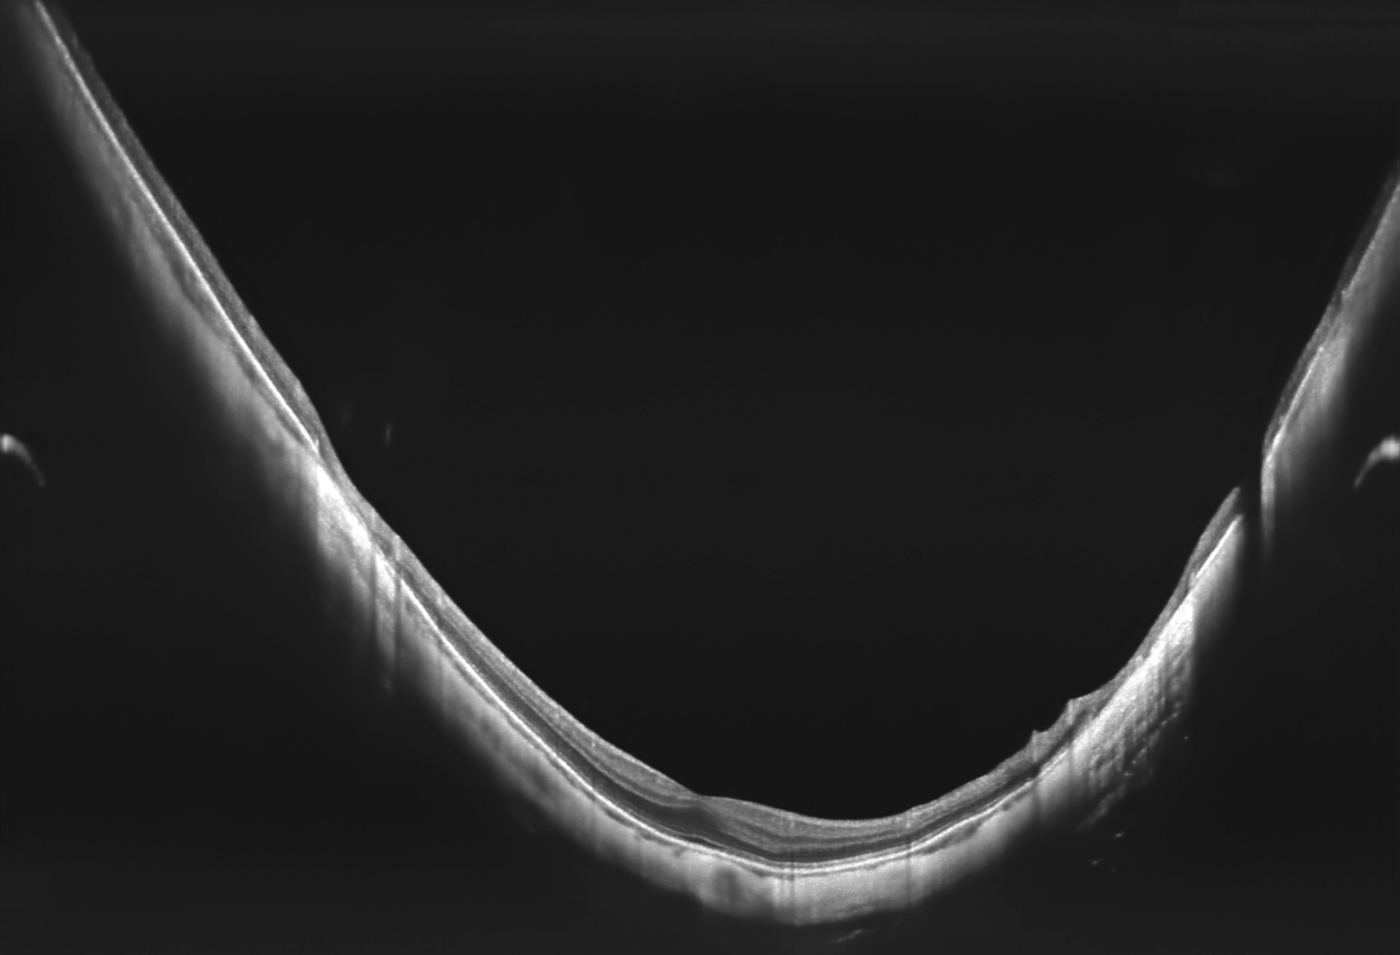

Anterior:

- Pachymetrie

- LASIK Flap Vermessung

- Kammerwinkelmessung

- Weitwinkel-Scans

Zusätzlich existiert ein Scanprogramm zur detaillierten Darstellung der Vorderkammer.

Das OCT-Topographie-Modul (T-OCT) ermöglicht eine umfangreiche Analyse der beiden Grenzflächen der Hornhaut. Zu den wichtigsten Analysen gehören die Ermittlung der Krümmungsradien (K1 und K2) der Hornhaut sowie die daraus resultierende Brechkraft der Hornhaut. Die Werte vervollständigen das in Version 8.0 veröffentlichte OCT-Biometrie Modul (B-OCT) der Copernicus REVO Reihe. Für die Auswertung der Ergebnisse stehen eine Vielzahl unterschiedlichster Darstellungen zur Verfügung. Die T-OCT-Technologie basiert auf dem Prinzip des Ray Tracings. Dabei wird neben der Vorder- und Rückfläche der Hornhaut auch die korrespondierende Hornhautdicke ermittelt.